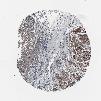

STOMACH CANCER - Protein expressioni

A mouse-over function shows sample information and annotation data. Click on an image to view it in a full screen mode. Samples can be filtered based on level of antibody staining by selecting one or several of the following categories: high, medium, low and not detected. The assay and annotation is described here.

Note that samples used for immunohistochemistry by the Human Protein Atlas do not correspond to samples in the TCGA dataset.

Antibody stainingi

Antibody staining in the annotated cell types in the current human tissue is reported as not detected, low, medium, or high, based on conventional immunohistochemistry profiling in selected tissues. This score is based on the combination of the staining intensity and fraction of stained cells.

Each image is clickable and will lead to virtual microscopy that enables deeper exploration of all samples and also displays staining intensity scores, fraction scores and subcellular localization as well as patient and tissue information for each sample.

Antibody HPA007264

Staining

High

Medium

Low

Not detected

Intensity

Strong

Moderate

Weak

Negative

Quantity

>75%

75%-25%

<25%

None

Location

Nuclear

Cytoplasmic/membranous

Cytoplasmic/membranous,nuclear

Adenocarcinoma, NOS

Adenocarcinoma, High grade